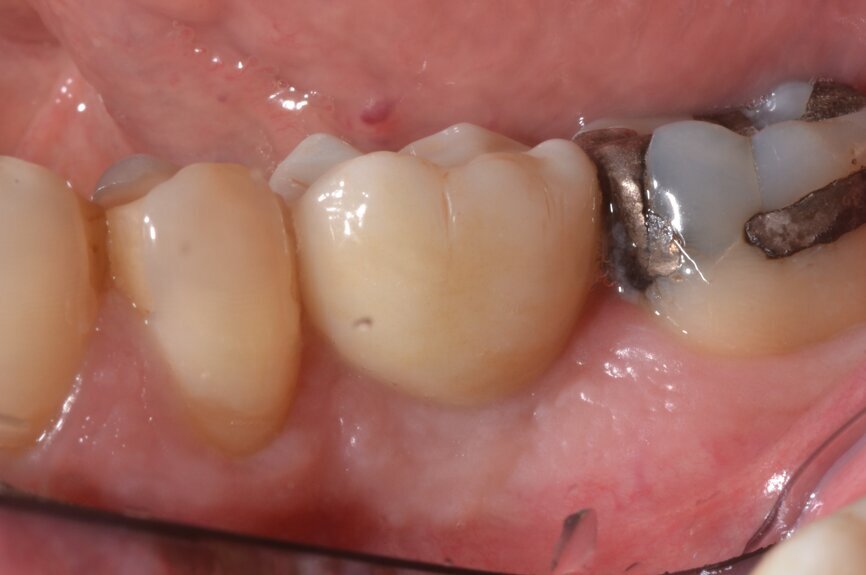

The patient, a 67-year-old non-smoking man without any relevant medical history, was referred to the office with a missing tooth (#36) due to persistent apical periodontitis. The tooth had been extracted more than one year prior to the procedure and the molar site was well maintained and fully healed (Fig. 1). A CBCT scan showed that the patient had favourable bone availability (Fig. 2), on which basis a one-stage placement of a 5.5 × 10.0 mm Straumann BLX implant was planned. After surgically installing the implant (Figs. 3–7), Salvesen allowed the surrounding soft tissue to mature and heal for six weeks (Fig. 8). He then removed the healing abutment to begin the prosthetic procedures for a temporary crown (Figs. 9 & 10). A stone master cast was made in the laboratory, and a temporary screw-retained PMMA crown was manufactured over a Straumann wide base temporary abutment for the crown (Fig. 11) and placed on to the implant (Figs. 12–14).

Fig. 1: Panoramic radiograph confirming the well-maintained anatomical conditions one year after tooth extraction.